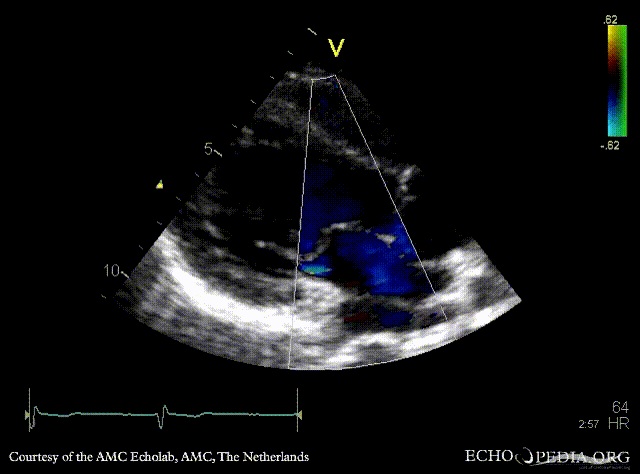

E00576.gif E00577.gif

PLAX: dilated coronary sinus PLAX with Color Doppler: pulmonary vein drainage into coronary sinus, connection with left atrium